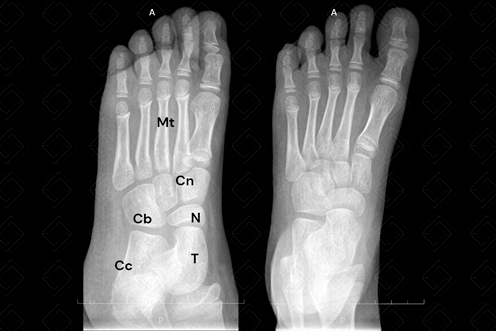

Descrição da figura: Radiografia do pé em AP e médio oblíquo evidenciando as falanges distais, proximais e médias, metatarsos (Mt), cuboide (Cb), cuneiformes (Cn), navicular (N), tálus (T) e calcâneo (Cc).